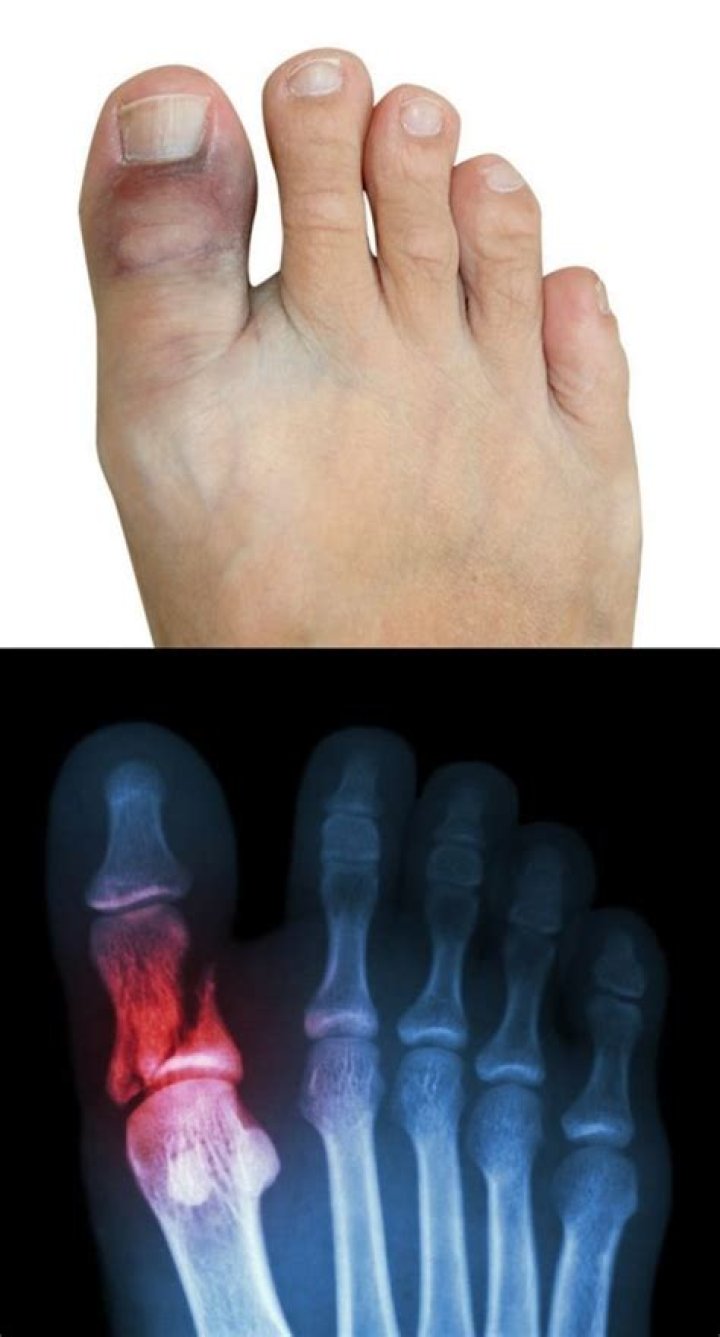

What does a sprained toe look like?

A sprained toe shouldn't look dislocated. It will still swell, but will likely have less bruising. A sprained toe may be painful for several days, but should then begin to improve. One other key difference between a break and a sprain is the location of the pain.

What's a broken toe look like?

Broken Toe Symptoms

Bruising of the skin around the toe may also be noticeable. The toe may not look normal, and it may even look bent or deformed if the broken bone is out of place. It may be difficult to walk because of the pain, especially if the big toe is fractured. Shoes may be painful to wear or feel too tight.

What does a bruised toe mean?

Bruised toes or foot can also be swollen, painful, and often appear purple or blue. A bruised toe can be caused from a broken toe and fracture. A broken foot or ankle can also cause bruises on top of the foot. Read below for more information on causes and treatment options.